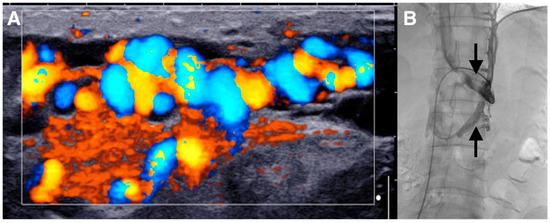

Figure 2. (A,B) Subsequently, a contrast-enhanced computed tomography (CT) imaging study with frontal reconstructions was obtained to evaluate the vasculature. The CT scan did not demonstrate a left testicular vein arising from the left renal vein. The left testicular vein at the level of the inguinal canal was visualized feeding the left-sided varicocele (arrows).